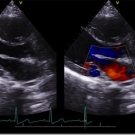

A 20-year-old woman presented to the clinic with midsternal chest pain radiating to the left arm.